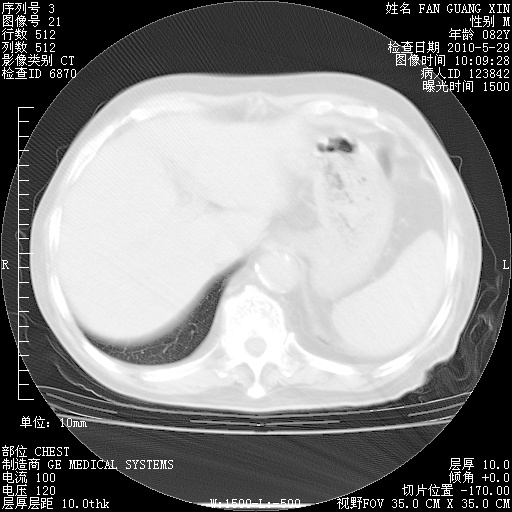

再治疗10天后的肺部CT

再治疗10天后的肺部CT 纵膈窗

阅读此次胸部CT,肺间质渗出性改变较入院时有吸收。目前从体温、白细胞、中性分叶明显增高,肯定存在细菌感染(发生医院感染哦,若无消化道及泌尿系统等感染的依据,肺部感染可能大)。若你院头孢哌酮舒巴坦钠耐药率较高,同意你的方案,若48小时体温仍高,可考虑使用碳青霉稀类抗菌药物,同时可予超声雾化、注意滴数时加大液体量。白蛋白33.30g/L较低哦,需加强营养等支持治疗。